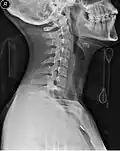

Vista lateral Radiografía del cuello con collarín cervical. -